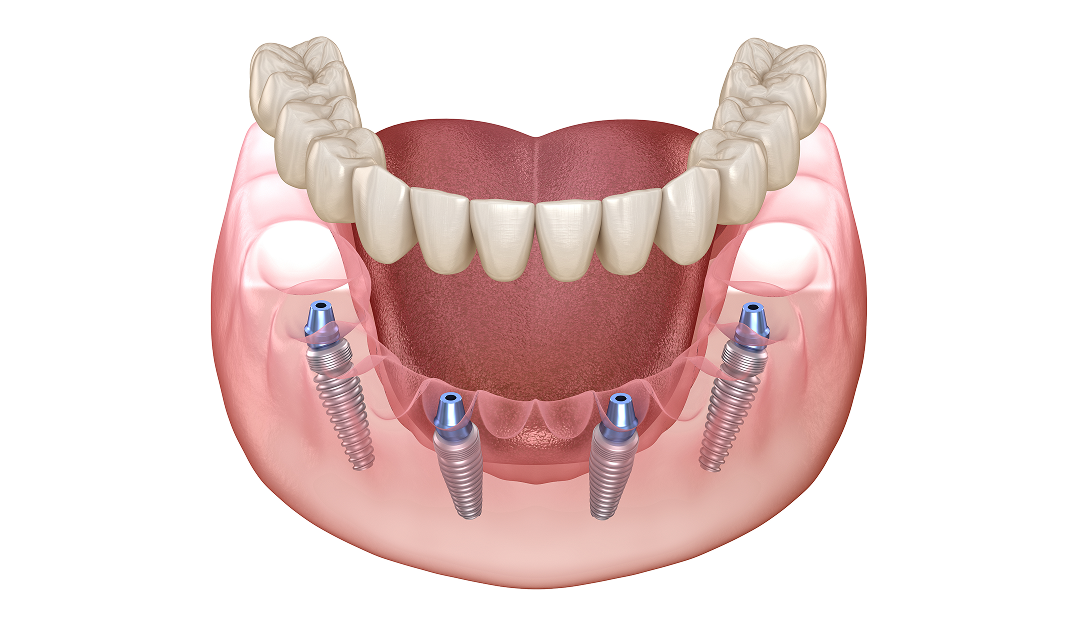

All-4-U 임플란트는 기존의 ‘All-on-X’ 개념에

서울하늘에치과만의 ‘UV 임플란트’와

‘100% 디지털 시스템’을 더해 탄생한,

새로운 개념의 혁신적인 치료이자 환자 맞춤형 솔루션입니다.

• · 틀니와 달리 완전 고정식 구조로 탈착이 불필요

• · 전체 임플란트보다 적은 개수로 비용과 시간이 크게 절약

• · 뼈이식을 최소화하여 수술 부담과 통증을 낮추고, 회복 기간 단축